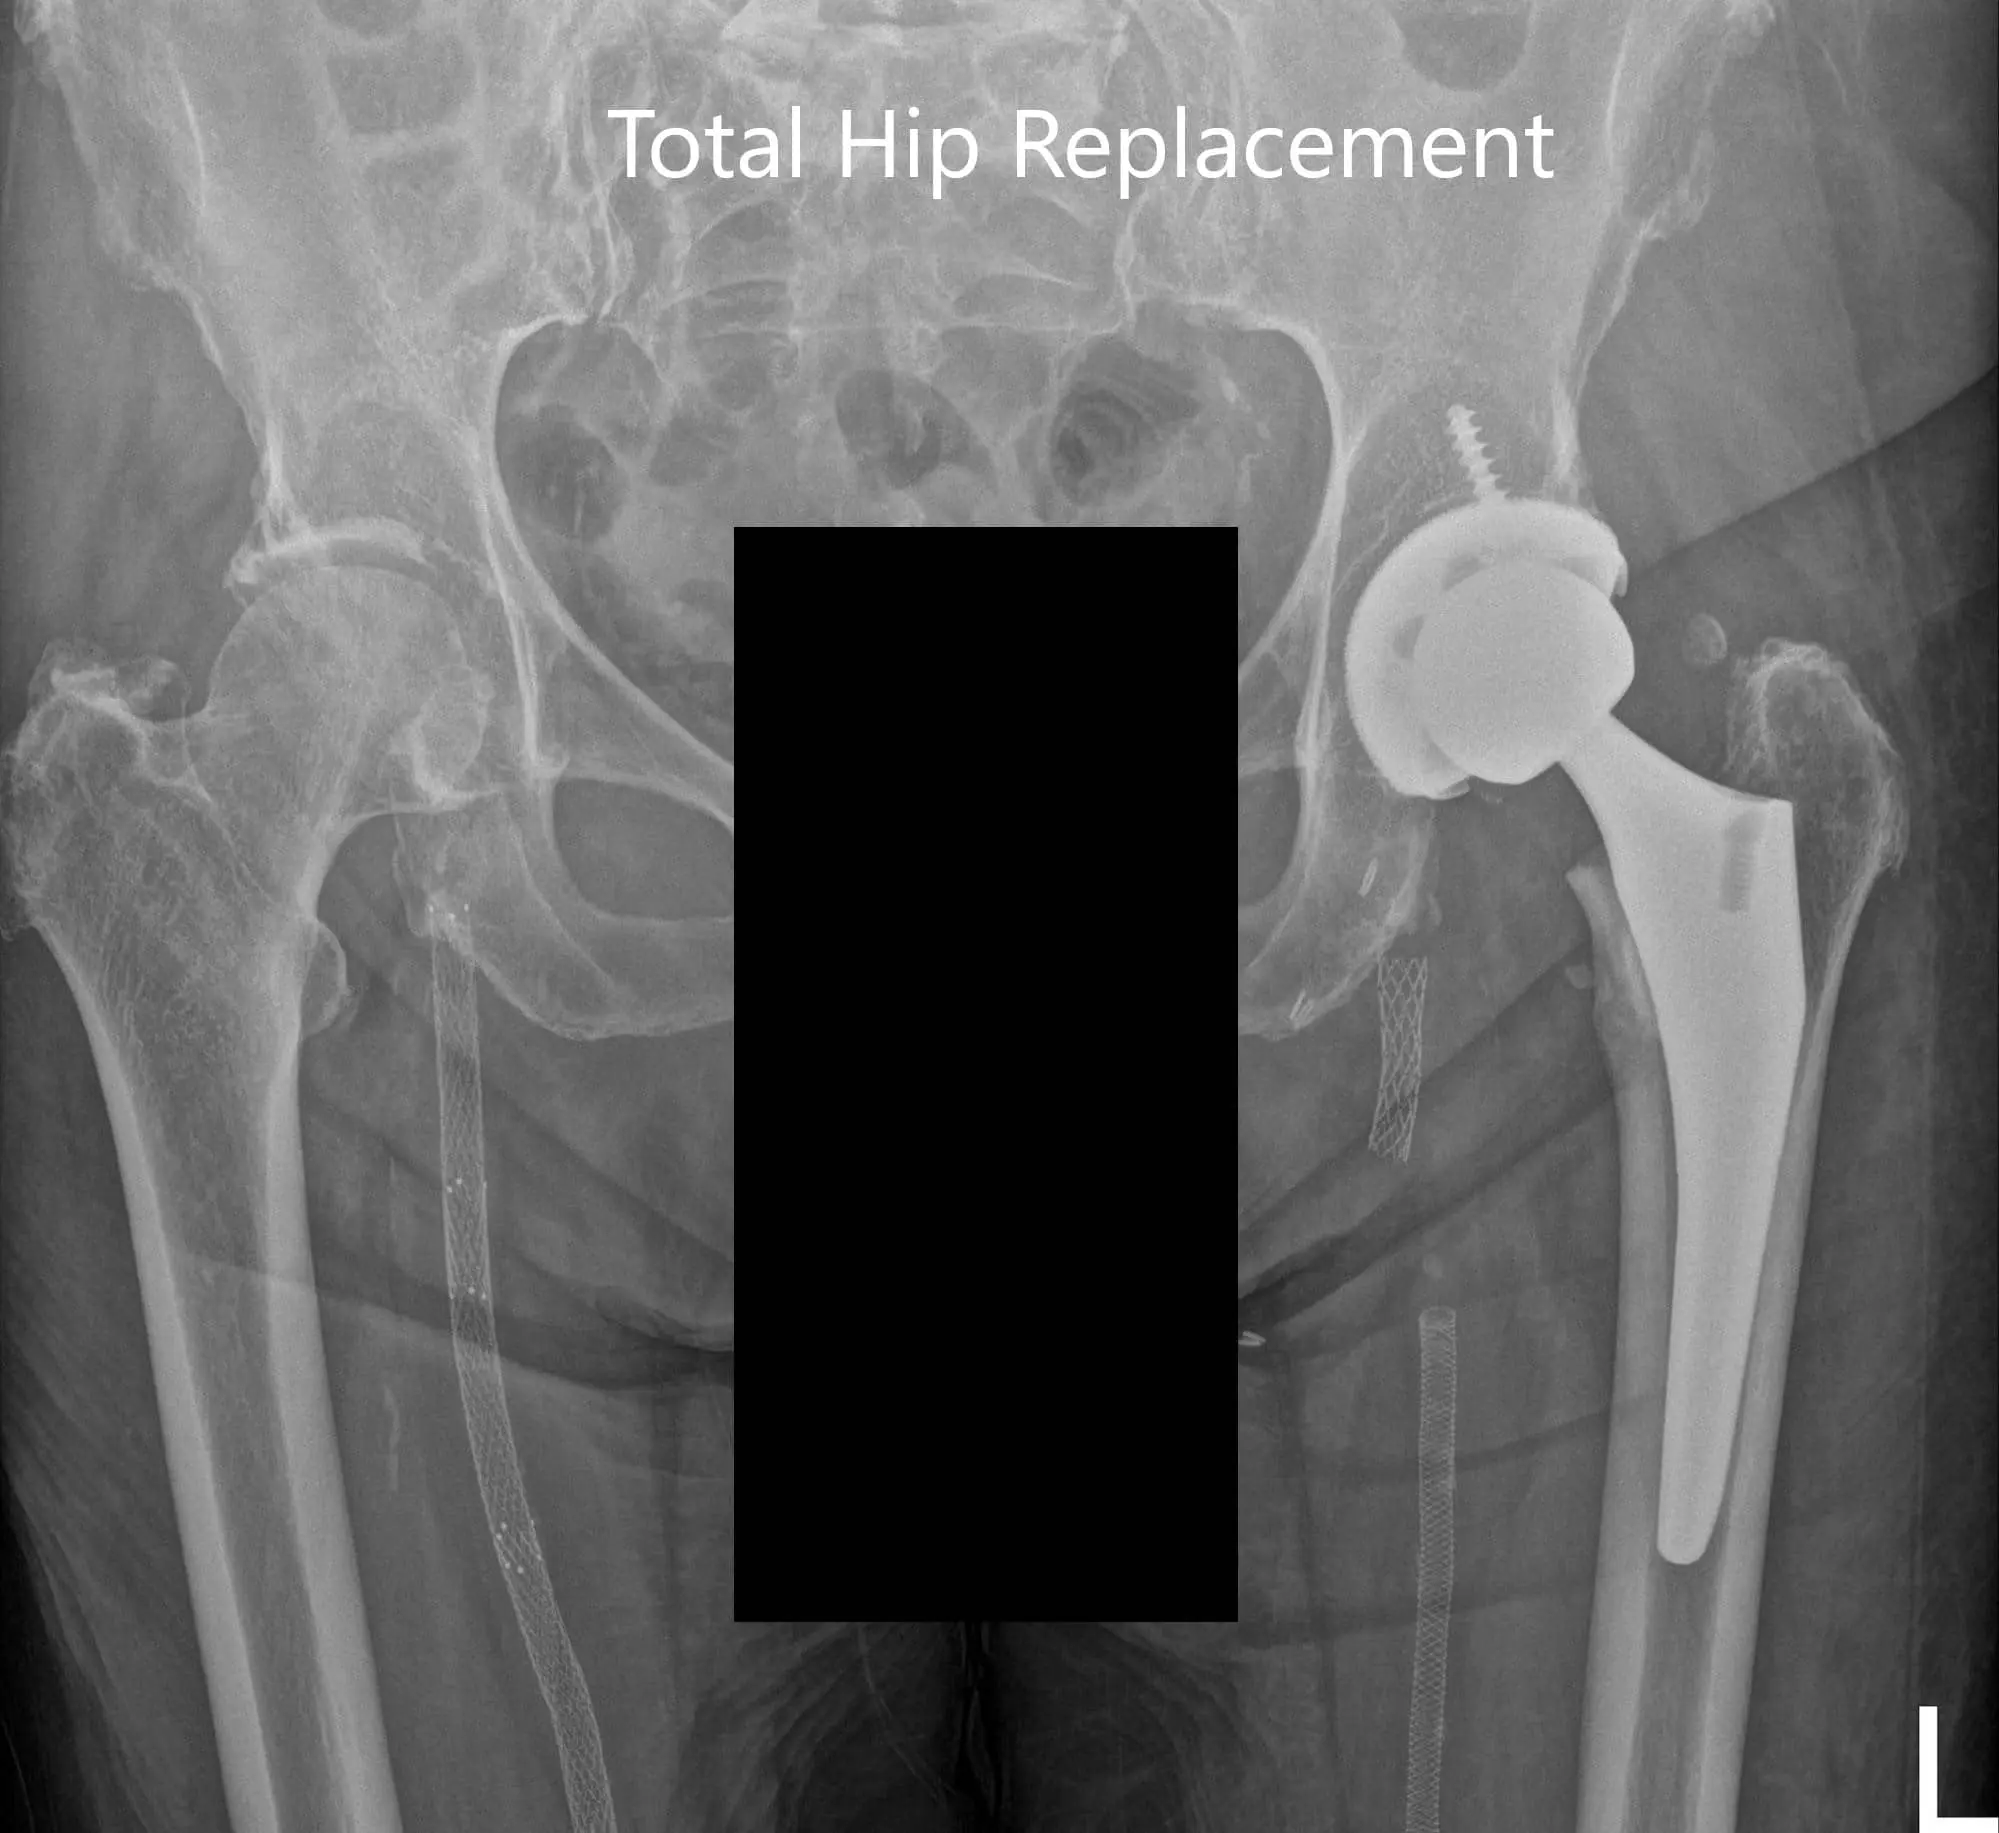

Postoperative X-ray images showing AP and lateral images

The postoperative recovery was excellent with the pain well managed with medications. He was started on aspirin 325mg for deep vein thrombosis prophylaxis. Weight-bearing was allowed as tolerated with support. The patient’s surgical wound staples were removed uneventfully. His physical therapy was focused on gait training, strengthening of muscles and range of motion exercises.

Upon three months follow up, he demonstrated a full range of motion with no pain. He complained of mild stiffness and was advised to continue physical therapy and home exercise program. He was happily back to activities he enjoyed. The increased mobility made him happy and more inclusive in his family.